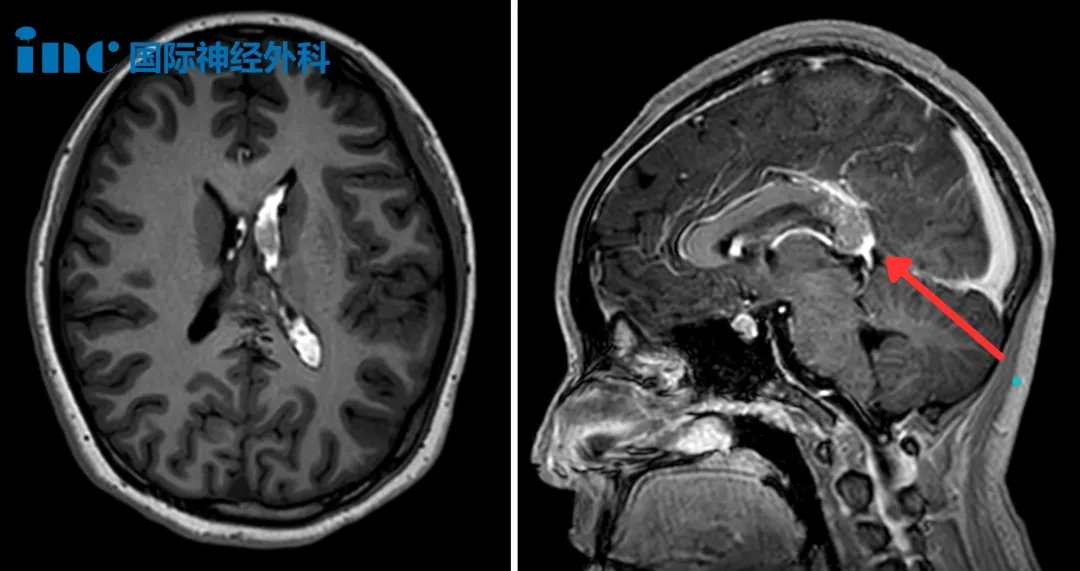

小蕊被父母紧急送往医院,头颅CT检查结果提示脑出血,而在之后的MRI结果瞬间将整个家庭推入了绝望的深渊——胼胝体压部藏着一个较大的动静脉畸形。

三天后,医生拔除了右侧引流管,只保留左侧继续引流脑嵴液。而当日的MRI检查揭开了更棘手的真相:胼胝体压部存在一个22mm×15mm的橄榄形动静脉畸形(AVM)。

更令小蕊父母揪心的是,这片畸形血管异常弥散,没有明确的边界。与正常脑组织交织在一起,这就使得手术难度极高!

术后第一天,小蕊就从ICU转出至普通病房。术后MRI图像清楚显示:AVM已被完全切除,脑室内出血也已清除。小蕊临床状况良好,很快就恢复了正常活动。